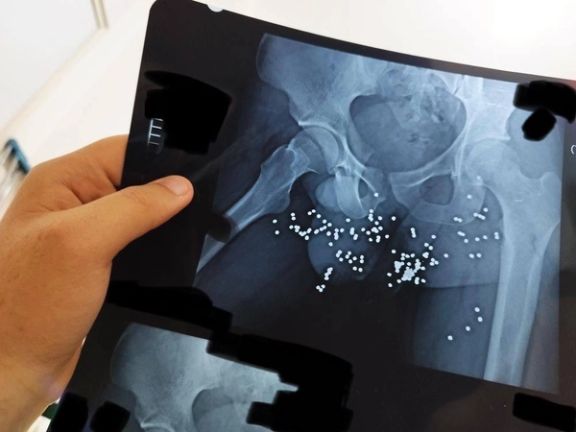

In addition to photos and videos of the injuries, the batch includes dozens of x-ray images and CT scans of pellets and slugs in the head, neck, chest and legs of the protestors. The Islamic Republic has killed many protesters with rubber bullets and metal pellets and blinded so many others.

The regime’s security forces have been extensively using cartridges of shotshell loaded with numerous small balls or birdshots, or medium-sized buckshots as well as single large solid projectiles known as a slug to quash the nationwide protests, ignited by the death in custody of 22-year-old Mahsa Amini in September 2022.